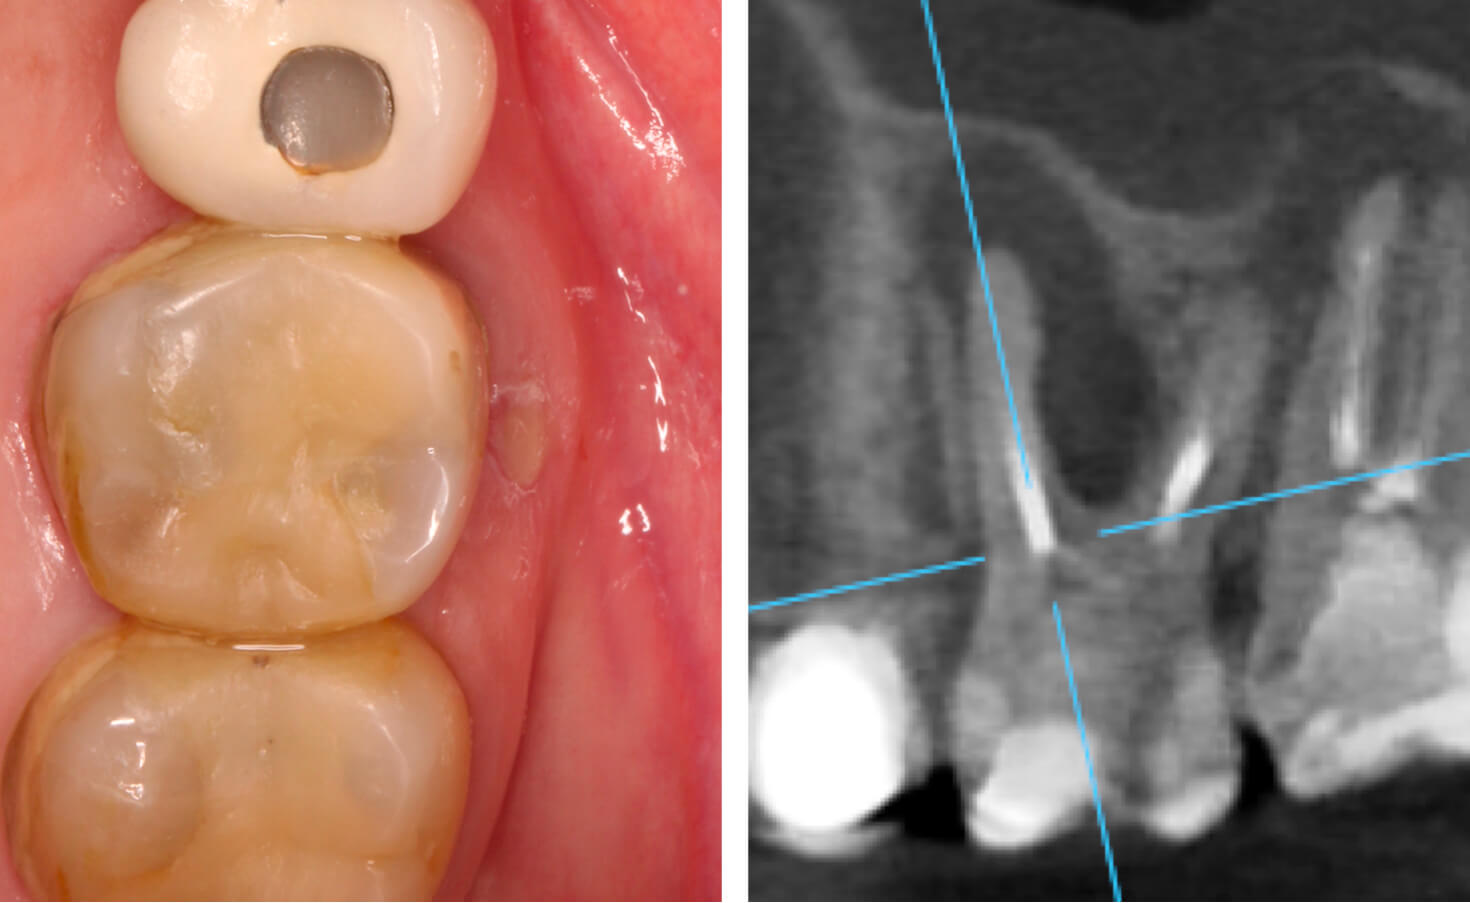

1. A case of tooth #16 presenting with chronic apical periodontitis featuring extensive mesiobuccal root periapical pathology (4-5mm lesion) and draining sinus tract, with evidence of prior incomplete endodontic treatment. (Image 1-4)